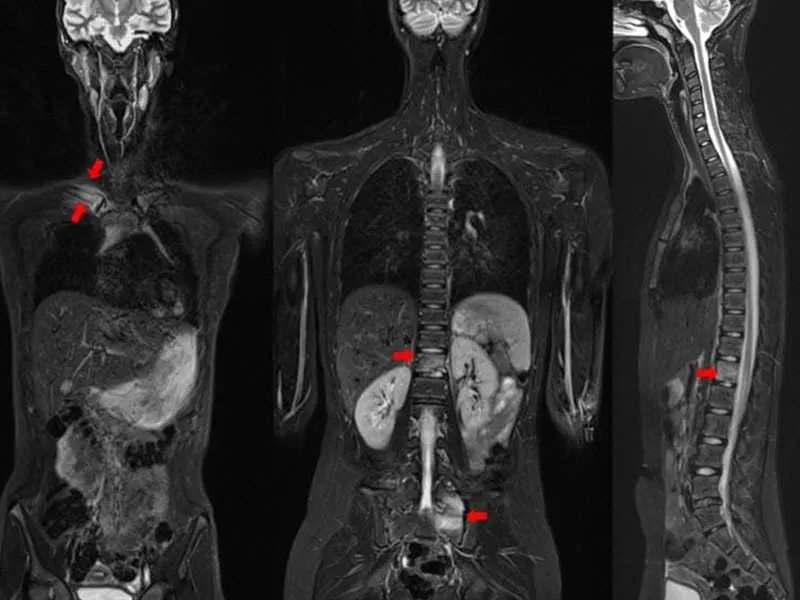

Tüm vücut MR, genellikle hastalıkların erken teşhisi ve yayılımının değerlendirilmesi amacıyla çekilir. Özellikle kanser taramaları, inflamatuar hastalıklar, enfeksiyonlar ve dejeneratif hastalıkların tespitinde kullanılır. Ayrıca, vücutta mevcut olan anormalliklerin detaylı bir şekilde incelenmesi için de tercih edilir.

Tüm vücut MR, kanser şüphesi olan hastalarda, inflamatuar hastalıklarda, enfeksiyonların yayılımını belirlemek için ve dejeneratif hastalıkların teşhisinde kullanılır. Ayrıca, kronik ağrıların kaynağını tespit etmek, sinir sistemi hastalıklarını ve damar problemlerini değerlendirmek amacıyla da uygulanabilir.

Tüm vücut MR ile kanser türleri, tümörlerin yayılımı, inflamatuar hastalıklar, enfeksiyonlar, dejeneratif hastalıklar, sinir sistemi bozuklukları ve damar hastalıkları teşhis edilebilir. Bu yöntem, özellikle erken teşhis gerektiren hastalıklarda büyük önem taşır ve doktorların doğru tedavi yöntemini belirlemelerine yardımcı olur.